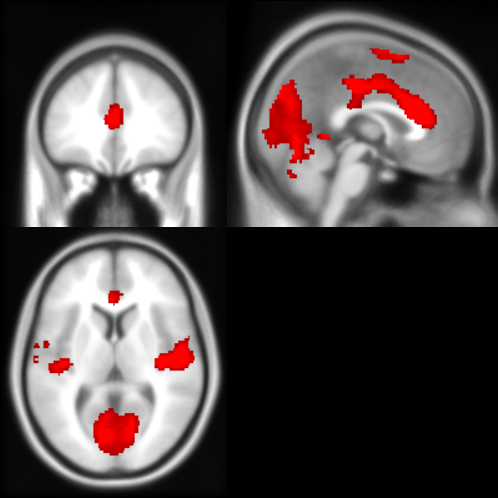

I've noticed that the overlays I project onto Surf Ice have more smoothing than I would expect; for example, an activation that lies mainly within the dACC in a volumetric view shows up as extending deep into the corpus callosum in Surf Ice. I see an option in SurfIce under "Preferences" that says "Smooth voxel-based images," but it doesn't seem to affect the overlay if I uncheck it. Is there a way to prevent SurfIce from adding any smoothing?

This is a voxelwise dataset (i.e., I am painting a NIFTI dataset onto the template). It is also a cluster corrected image, so only voxels surviving the cluster threshold should be displayed.

for example, in the following image the threshold for the reddish overlay has been set to 2..12, setting the range to 1..12 will lead to a larger region seurviving the threshold and a range of 6..12 would lead to a more focal region. Choose you threshold based on your correction for multiple comparisons.

contrast_surfice.png Download

contrast_volumetric.png Download